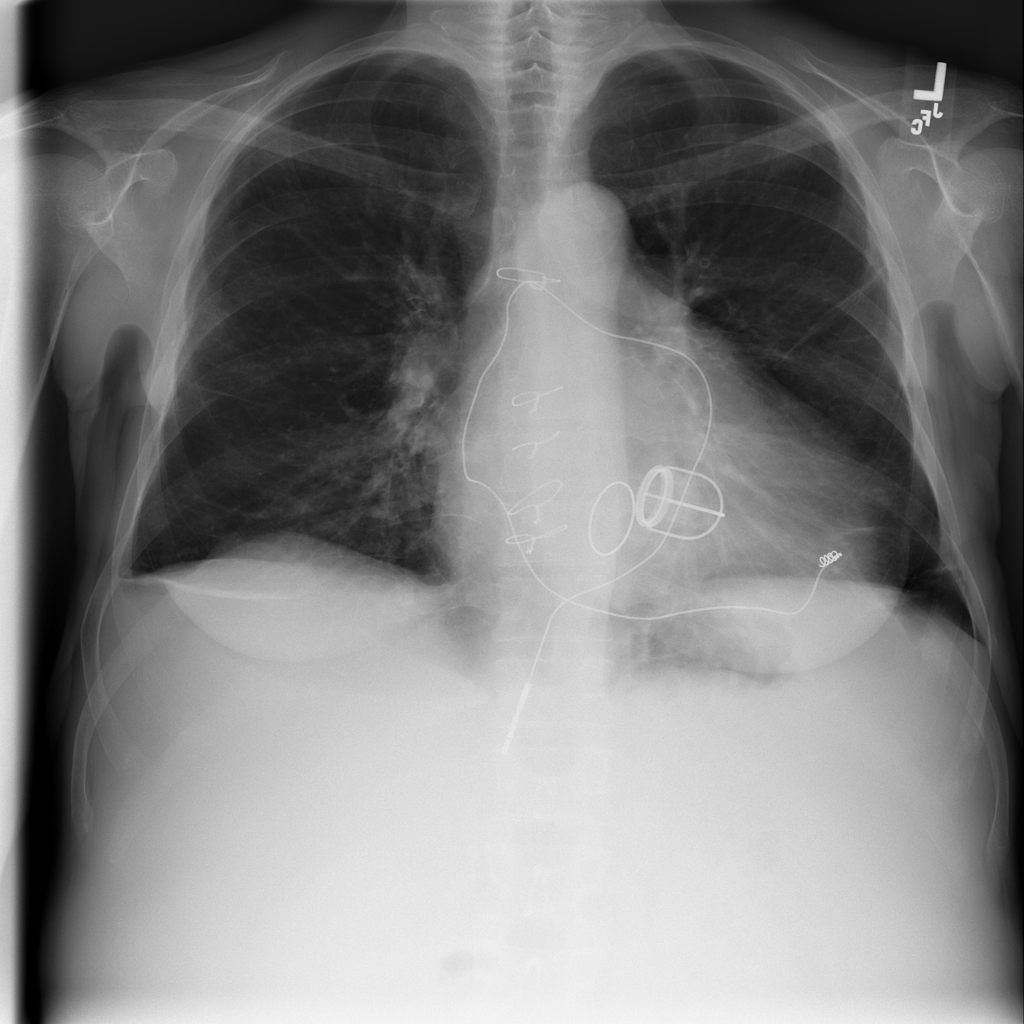

Cardiomegaly

Cardiomegaly means the heart appears enlarged on the chest X-ray. It is a descriptive imaging finding that can be related to heart strain, chronic pressure or volume changes, or even projection effects.

Showing up to 90 reference images for Cardiomegaly.

PAT-F3E7 · IMG-000Cardiomegaly

PAT-F3E7 · IMG-000

PA